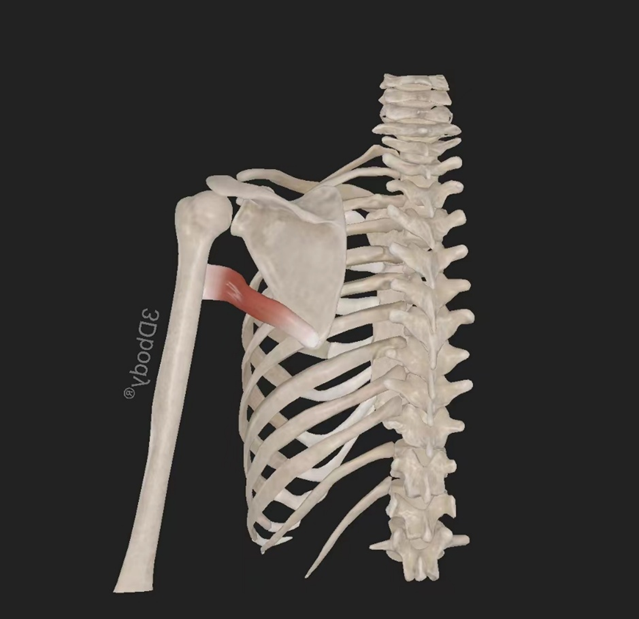

冈上肌:起自冈上窝,穿过肩峰和喙肩韧带,止于肱骨大结节上部部。由肩胛上神经(C5—6)支配。作用:使肩关节外展。

肩胛下肌:起自肩胛下窝(肩胛骨前面),止于肱骨小结节。由肩胛下神经(C5—6)支配。作用:使肩关节旋内、内收。

4、外展:肩关节的外展由三角肌(主要是其中间束)及冈上肌完成。当肩处于内旋或外旋位置时,三角肌在最外侧的部分是外展的主要肌肉,当肩外旋时外展肌力要更强些。

5、内旋:内旋肌主要是肩胛下肌,当肩关节处于特定体位时胸大肌三角肌前部纤维、大圆肌及背阔肌也有一定的内旋作用。